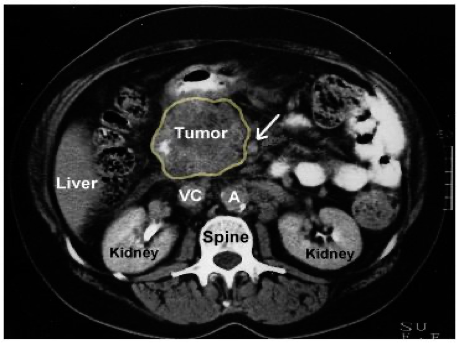

Investigations of pancreatic tumors

Imaging

CT scan and MRI can assess the site of the tumor in the pancreas and the evidence of metastases or local invasion by the tumor (staging)

Tumor in the head of pancreas

SMA - Small bowel supply from arrow -